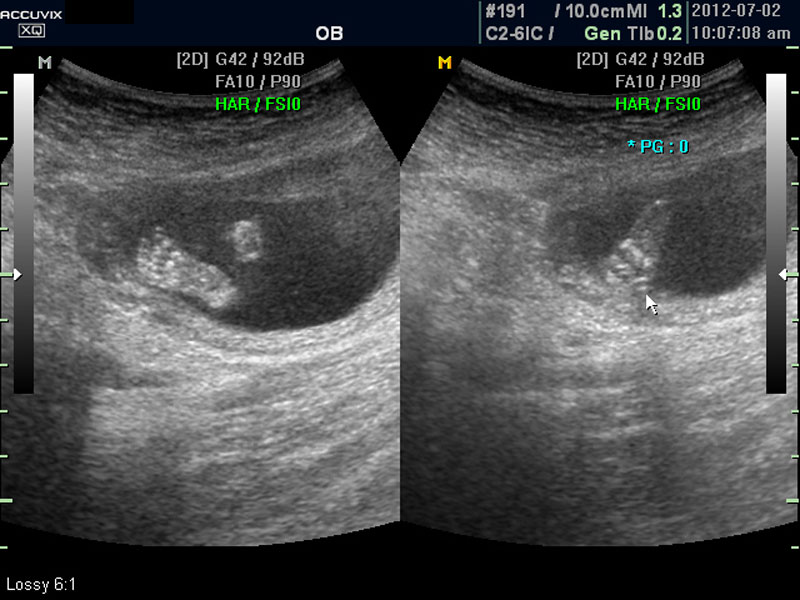

임신 중기의 초음파에서는 아기의 크기, 심장 박동이나 활동의 정도, 각종 장기의 구성이 정상인가 하는 것을 살펴 보게 됩니다.

태아의 대부분 장기는 임신 중기에는 이미 다 형성이 되고 이때부터는 크기가 커지면서 기능이 갖추어지는 시기입니다.

따라서 가장 여러가지 소견을 자세히 살펴 보아야 하는 시기에 해당하며 기형아 검사라고 하는 혈액 검사나 양수 검사도 보통 이 시기에 하게 됩니다.

우선 초음파 사진에서 볼 것은 태아의 크기가 정상인가 하는 것입니다.

대신 첫번째 사진에서 보는 것처럼 태아의 전체 모습 특히 태아의 등쪽이나 복벽의 이상은 없는지 신경관 결손 등으로 인한 종괴가 있지는 않은지 관찰하며 태아의 복벽이나 등쪽은 일직선으로 매끈하게 보이는 것이 정상입니다.

첫번째 사진에서는 하지 부분은 대퇴부만 일부 보이며 이는 태아가 다리를 구부리고 있고 팔도 이리저리 움직여 머리 위나 목 쪽으로 두는 경우가 많아서 한번에 전체 모습을 찍기가 어려운 경우가 많습니다.

따라서 부분 부분 살펴 보면서 해당 모습을 찍어서 저장하거나 인쇄하여 드리기도 하는 것이며 아래 사진은 태아의 다리 부분을 찍은 것입니다.

태아에 대한 관찰이 끝나면 태반의 위치와 양수의 양을 살펴 보는데 아직 태반의 위치는 고정된 것이 아니라 크게 의미는 없지만 이때부터의 위치는 대체로 임신 후반까지 크게 바뀌는 것은 아니며 또한 완전 전치 태반과 같은 경우는 임신 중기부터 출혈등의 증상이 나타날 수 있어 관찰이 필요한 대상입니다.

화면에서는 위쪽에 하얗게 균일하게 보이는 것이 태반의 모습입니다.

태반은 실제로 보면 피자처럼 둥그런 원판 모양이며 임신 후기로 갈수록 태아와 마찬가지로 크기가 커지고 두꺼워집니다.

양수의 양은 태아의 건강과 관련된 지표로 너무 많거나 너무 적으면 좋지 않은데 그 절대양을 측정할 수는 없어서 양수가 많은 부분의 깊이를 측정하거나 혹은 개략적으로 전체에서 차지하는 부분을 봐서 이상 여부를 판단합니다.

사진에서 검게 보이는 것이 양수입니다. 양수에 대하여는 색깔이나 밀도 등 다른 요소는 알기 어려워서 그 양만 가지고 판단을 하게 됩니다.